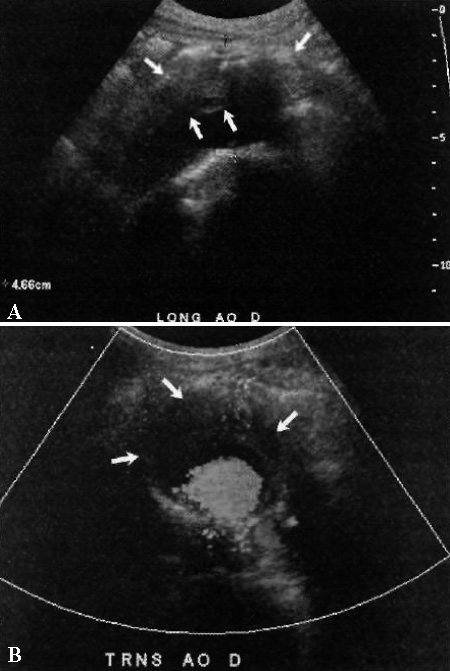

Фото 2. Аневризма брюшного отдела аорты. А – продольное медиальное ультразвуковое изображение аорты: стрелками обозначены гипоэхогенные пристеночные атеромы на фоне анэхогенного просвета. Курсорами отмечен диаметр по короткой оси от стенки до стенки, который составляет 4,7 см. В – цветовая допплерограмма: поперечный вид аорты; стрелками обозначена пристеночная атерома (просвет сосуда цветной)